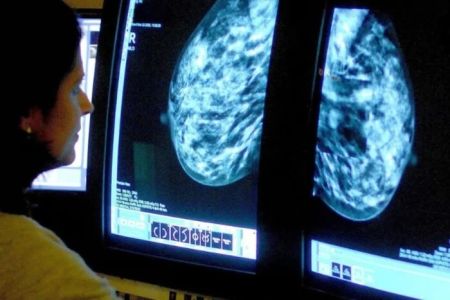

Рак є однією з найнебезпечніших хвороб сучасності, і деякі його види мають особливо агресивний характер. Визначення того, який вид раку…

Дослідники Каліфорнійського університету в Ріверсайді та Мічиганського державного університету розробили унікальний клас світлочутливих хімічних сполук, здатних знищувати агресивні пухлини, зокрема…